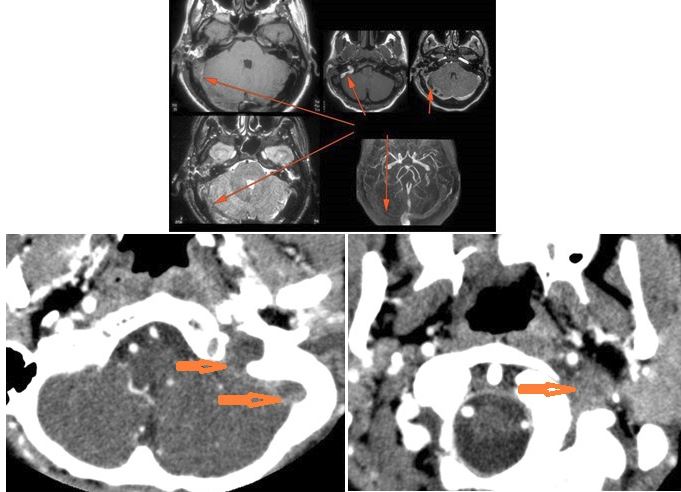

There is dural reactive or leptomeningeal enhancement involving the internal auditory canal and the 7th and 8th cranial nerves. [Yes/No]

There is dural reactive change along the floor of the middle cranial fossa or along the inner (intracranial) surfaces of the petrous portion of the temporal bone or clivus. [Yes/No]

There is a subperiosteal, subdural or epidural abscess along the floor of the middle cranial fossa or along the inner (intracranial) surfaces of the petrous portion of the temporal bone or tentorium or falx cerebri. [Yes/No]

There is likely meningitis involving the inferior temporal lobe or adjacent cerebellum or more remote meningeal sites. [Yes/No]

There is brain edema and/or evolving abscess present or, specifically, involving the inferior temporal lobe or adjacent cerebellum. [Yes/No]

There is evidence of thrombosis, thrombophlebitis or other occlusive or inflammatory process of the sigmoid sinus, transverse sinus, the vein of Labbe’ or jugular bulb or vein. [Yes/No]